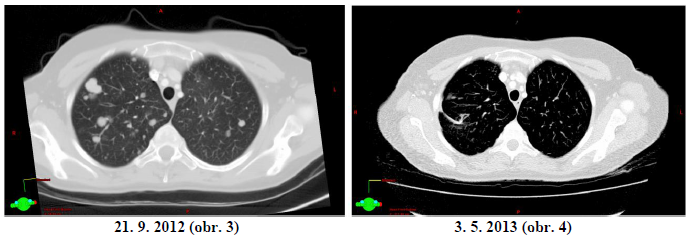

JH r. 1972, dg. 2010 ca mammae l.dx T2 N0 M0, pT2 pN0 pM0, histol.: invazivní duktální karcinom M8500/32, ER 60%, PR70%, Ki67 5%, HER2neu 1+, FISH nebyla nalezena amplifikace, prokázaná mutace BRCA2. Adjuvantní léčba byla ukončena 5/2011. 1. generalizace dle CT 21. 9. 2012 – mnohočetná meta ložiska do obou plicních křídel, největší do 22mm, (Obr. 3)

23. 10. 2012 – zahájena léčba weekly paklitaxel 80mg/m2 + Avastin 10mg/kg á 14 dní CT

(3. 5. 2013) - ložiska svědčící pro neoplazii nenacházíme – CR (obr. 4)

Závěr 1

Pacientka je v kompletní remisi. Léčba Paklitaxelem byla ukončena 3. 5. 2013. Od 4. 6. 2013 pokračuje léčba monoterapií Avastinem 10 mg/kg á 14 dní. Kontrolní vyšetření CT bylo provedeno 12. 7. 2013 – nadále kompletní remise. Další kontrolní vyšetření CT bude provedeno v listopadu 2013.